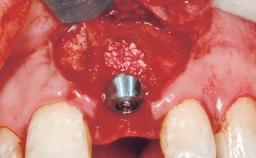

Immediate Placement of an Implant in a Maxillary Right Central Incisor Site

A 30-year-old female patient was referred to the office for the treatment of tooth 11. Her chief concern at the initial visit was to inquire, “Why is my tooth pink?” Upon clinical examination, it was determined that tooth 11 had a previous history of trauma and that the clinical crown had become noticeably pink in color as a result of internal resorption. This diagnosis was confirmed radiographically, indicating a large radiolucency involving the central and distal portions of the clinical crown. It was determined that restoration of this tooth was not possible, and that extraction was indicated. The presence of a mid-line diastema, which the patient wanted to reproduce, directed the treatment plan for tooth replacement utilizing a dental implant.

Bone Augmentation Horizontal|Simultaneous

Augmentation Materials Autogenous chips|Membrane

Placement Protocol Immediate implant placement

Socket Integrity Sufficient, with intact bone walls

Bone Volume Sufficient, with intact walls